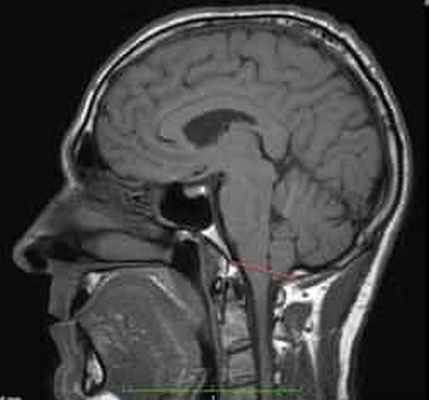

Рисунок 2.- МРТ пациента в 8 и 20 месяцев, на втором снимке можно наблюдать опущение миндалин мозжечка, которое появилось уже после первого МРТ. Huang P. “Adquired” Chiari I malformation. J. Neurosurg 1994. Это указывает на то, что, помимо наследственного и генетического фактора, существует фактор приобретенного заболевания.